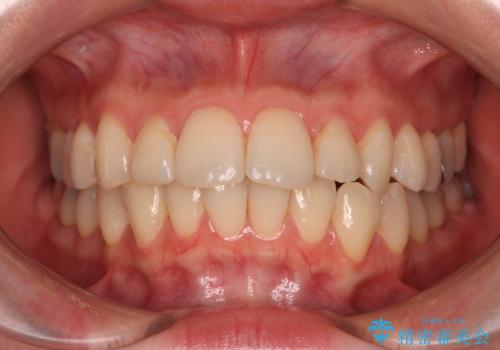

前歯のデコボコを短期間で解消 ワイヤー装置による抜歯矯正

- 上下前歯のデコボコを気にして来院された患者様です。

デコボコが強いため、非抜歯で矯正をすると出っ歯仕上がりとなるため、上下左右の第一小臼歯4本を抜歯することとしました。

当初予定は2年半程度と伝えていましたが、2年にも満たない期間で治療を終えることができました。